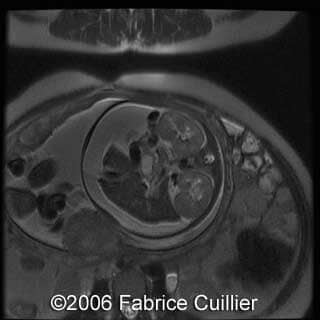

MRI images

Kidney"s enlargement

- Bilateral kidney’s enlargement without increased echogenicity. The corticomedullary differentiation seemed normal

At 37 week of pregnancy, a cesarean section was performed. Female baby was born weighting 5.1 kg wit the Apgar scores 1/1/1. The baby was referred to intensive care unit. The newborn’s abdomen was distended due to bilateral kidney’s enlargement. Postnatal scans confirmed prenatal findings of bilateral kidney’s enlargement. Renal and hepatic functions were abnormal. A puncture of the ascites was performed (>0.5 l), but anuria appeared after that. Despite of intensive neonatal care, the baby died on the first postnatal day due to circulatory collapse and respiratory distress. Parents refused the postmortem examination, but the kidney biopsy was done with the diagnosis of nephroblastomatosis.

Our final diagnosis was Perlman syndrome.